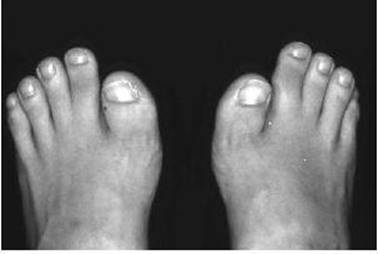

However the rare fibrodysplasia ossificans progressiva which has an unexplained short first toe (Figure 13.3) and widespread heterotopic bone formation, is associated with an excess of the bone morphogenetic protein 4 (BMP 4) gene which may be due to a deficiency of the BMP inhibitor genes, curiously named gremlin (DRM) and noggin. Also the progressive ankylosis gene ank produces intra-articular and peri-articular joint fusion in man and mice.

Figure 13.3 Short great toe characteristic of fibrodysplasia ossificans progressiva.